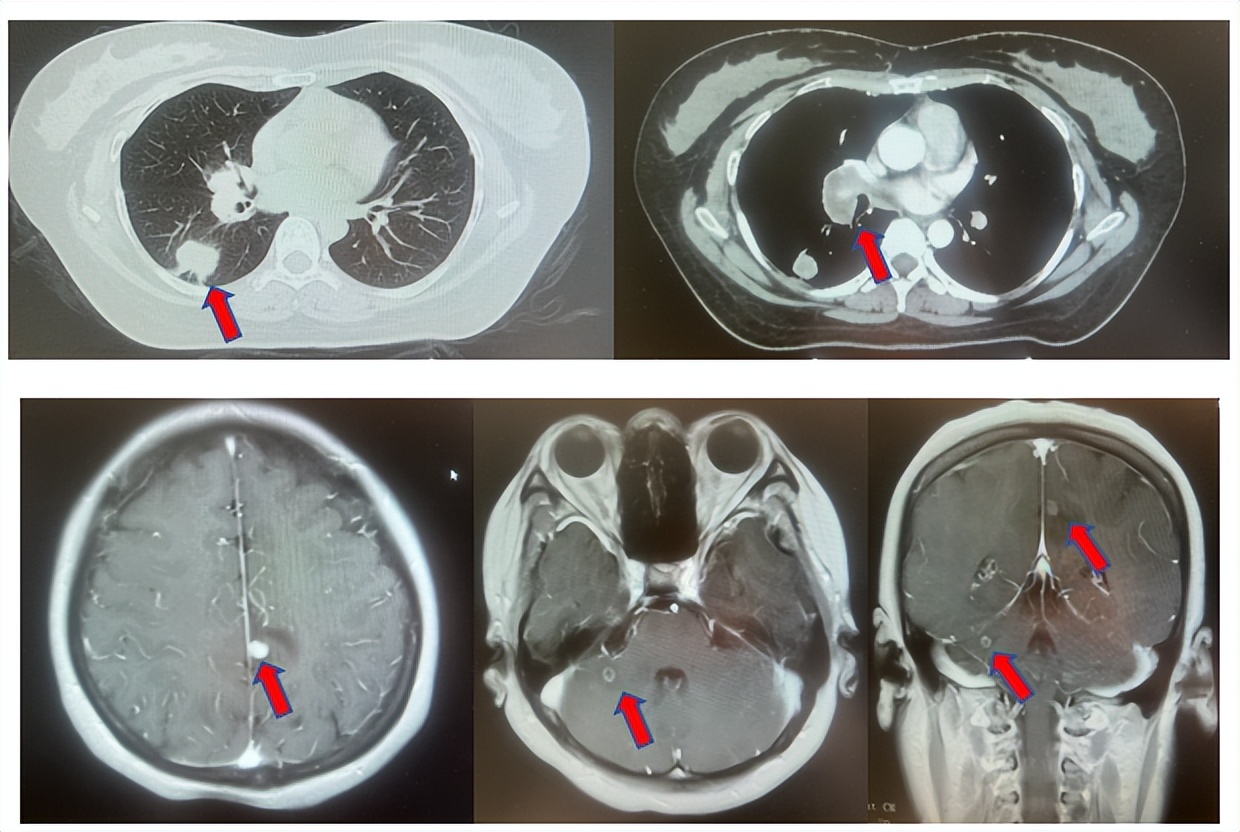

患者符合我科正在开展的“一项比较Durvalumab治疗与标准治疗(含铂化疗)用于PD-L1高表达晚期非小细胞肺癌患者一线治疗的III期随机、开放、多中心研究”的入组要求,经知情同意进入该试验,经随机进入化疗组,于2017年7月至2023年12月应用培美曲塞联合卡铂治疗6周期,后行培美曲塞单药维持治疗105周期,肺内CT现实右肺下叶病灶缩小90%,颅内病灶缩小100%,最佳疗效肺内病灶PR及颅内病灶达CR(图2),于2023年2月复查CT,肺内病灶逐渐增大,至2024年1月,疾病进展出组该临床试验,一线无进展生存为78个月。

图2:上两图分别展示2021年5月患者达到最佳疗效时肺CT肺窗及纵隔窗肺内病灶及肺门淋巴结影像,下三图表示最佳疗效时脑MRI影像

患者进入到二线治疗,该患者再次符合我科“优替德隆对照多西他赛治疗含铂化疗失败的局部晚期或转移性非小细胞肺癌的III期、开放、随机对照临床试验”经随机进入多西他赛组,截止至目前患者已行多西他赛治疗19周期,期间评效为SD(图3),二线无进展生存至今为14个月,患者总生存期截止目前超过92个月(整体治疗过程如图4所示)。

图3:上两图分别展示2024年1月患者一线进展时肺CT肺窗及纵隔窗肺内病灶影像,下两图表示2024年12月患者二线治疗间期评效时肺CT肺窗及纵隔窗肺内病灶影像